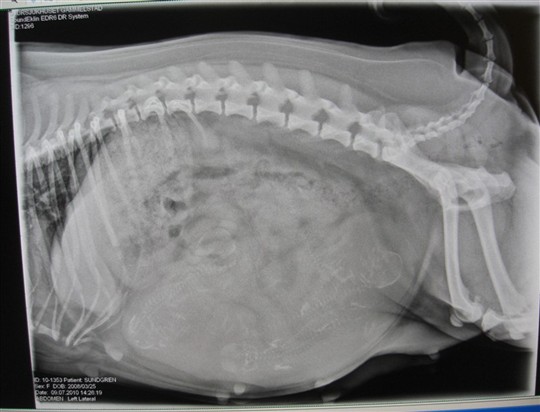

Och så till Doris...röntgat henne idag för att se hur många puppisar som finns där inne...och 5 små bäbismopsar finns det i magen

:) hoppas bara att allt med valpning ska gå bra:):)

Det är så varmt för henne nu och tungt med magen......